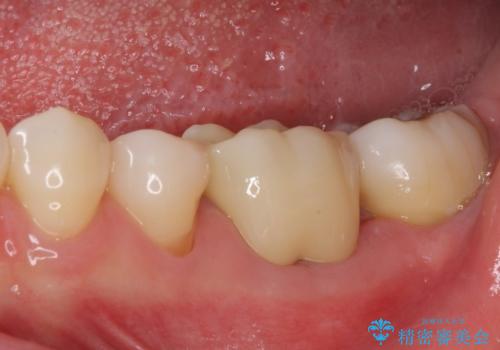

奥歯の虫歯 オールセラミッククラウンによる補綴治療

根管治療を終えた後には、今まで気になっていた痛みが消え、快適に日常生活を送れるようになりました。

痛みが取れるとともに、気になっていた大きな銀歯も自然なセラミックとなり、患者様には大変満足していただけました。